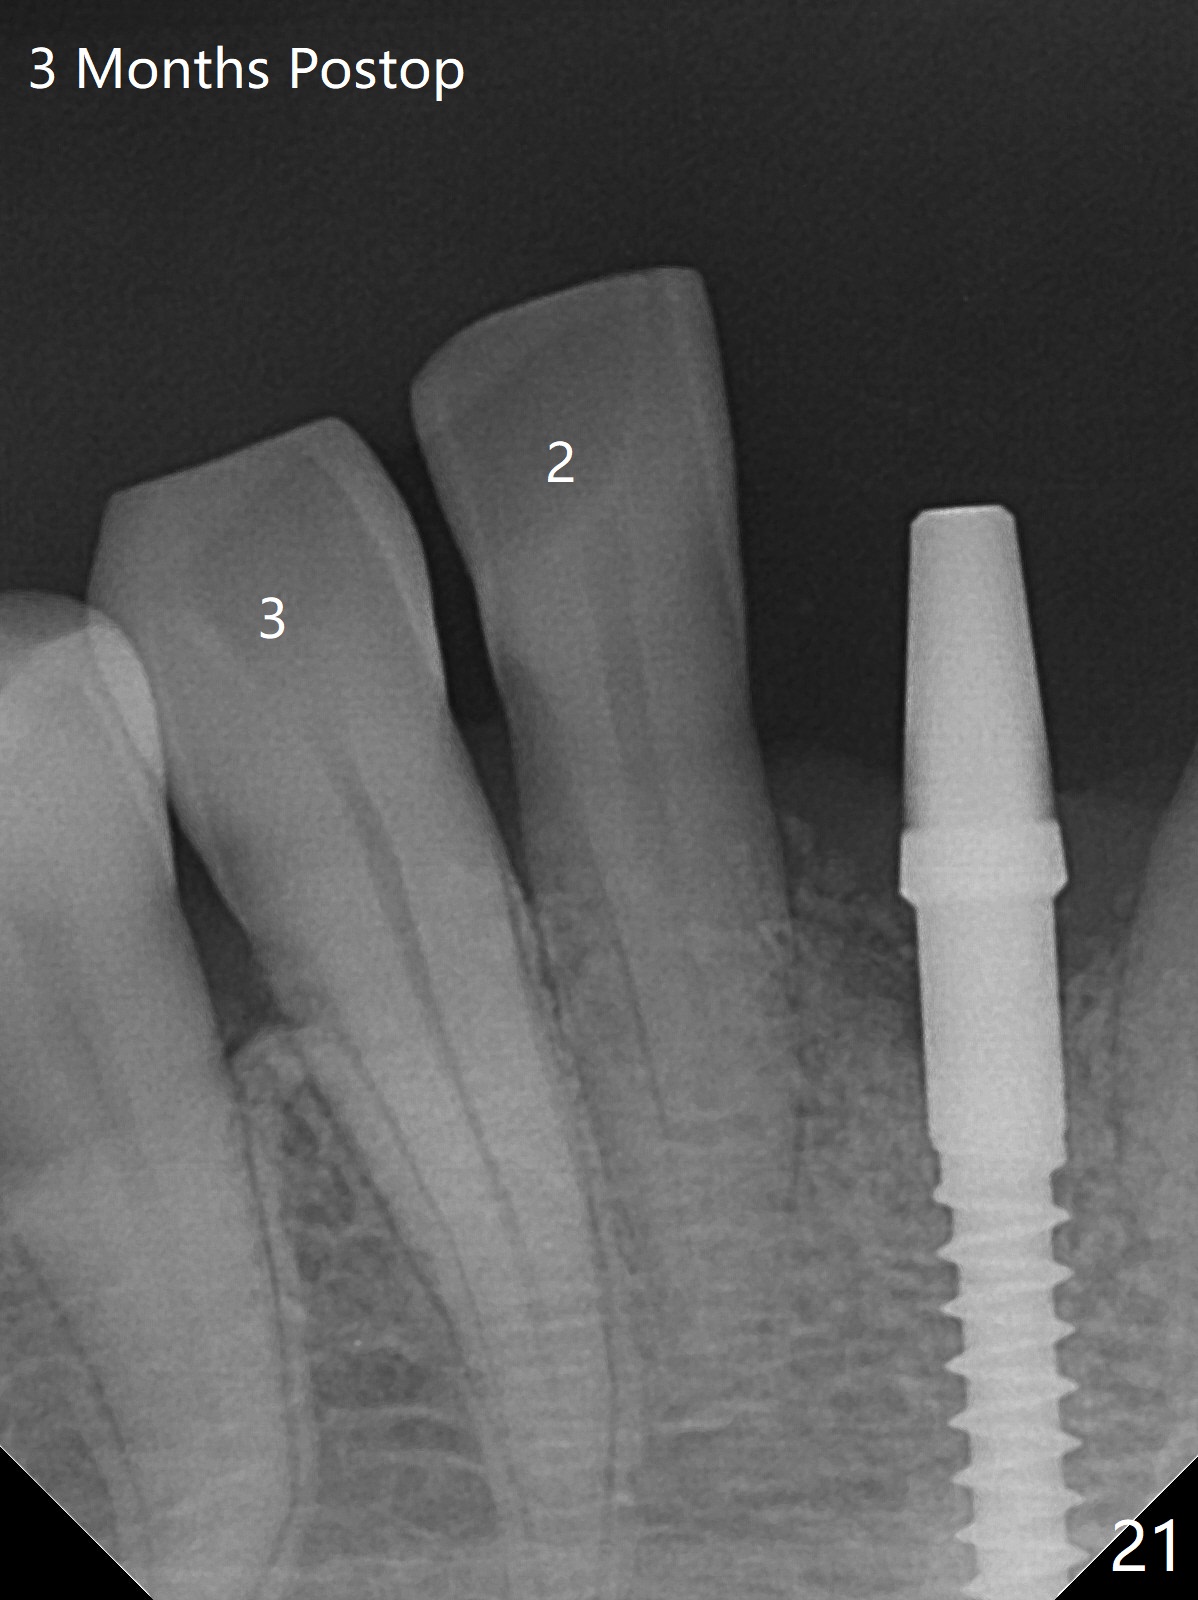

56岁女十分恐惧治疗,缺失右下1,其余切牙由于骨质吸收颊侧移位(图一:1,2),但是她不愿意拔除,同意右下1种植,牙周骨手术,植骨;植体整合后作为支抗,矫正移位下门牙。为了防止忘记舌侧瓣分离,先做舌侧切口(图二),然后颊侧瓣松弛分离(图三),包括使用前牙隧道刀(图四)切断颊侧骨膜,松弛到颊侧瓣能向舌侧牵拉3-4毫米(图五),舌侧瓣骨膜下广泛,深部分离(好像不能切断骨膜,图六),放置导板,磨平狭窄的牙槽嵴(图七:O(osteotomy)),植入2.5x12(4)毫米一段式植体(图八:故意舌侧植入,以便以后矫正),在颊侧骨板打多个出血洞(图八:箭头),然后把在平的器皿上形成的粘性骨板(sticky bone,图九),放置于植体和移位切牙周围(图十),接着使用消毒过的橡皮障punch(图十一(纸头相当于PRF膜;事先给助手示范))在三个PRF膜(图十二)打洞,套在植体和门牙上(图十三: 箭头),防止膜(图十四)和骨块(图十五,十六:*)移位,最后还必须使用最原始方法牙周敷料保护伤口(图十七)。术后9天,舌侧牙周敷料脱落,伤口稍微裂开(图十八)。术后18天撤除敷料,伤口裂开处有新鲜肉芽组织生长(图十九(*:下面是填入的骨粉,将是增宽的牙槽嵴(如果你是乐观主义者)),二十)。病人十分感激我们帮助她度过难关。她的确有sleep apnea,否定tongue thrust。术后三个月植体周围没有明显骨质吸收(图二十一至二十三),左下1,2轻度反合(图二十四),植体周围软组织健康(图二十五),5-5安置矫正器(图二十六,二十七,12 niti)。一周后下切牙向舌侧移动(图二十八),左下1,2反合纠正(图二十九)。再一周变化不大(图三十),植牙圈有些松动,两周后将重做临时牙冠,槽往舌侧移动。结果病人提前回来,植牙槽舌侧移位。一周后右下2不适(图三十一),尝试近中牵引(图三十二)。